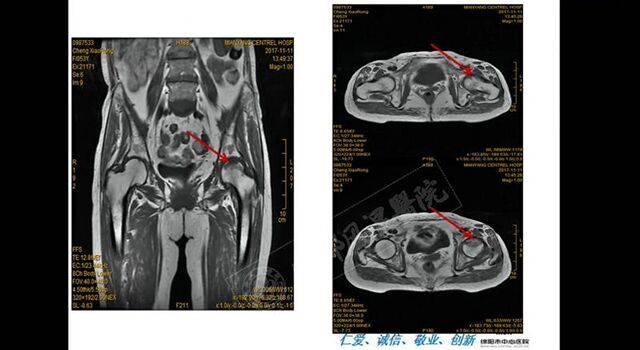

绵阳市中心医院免疫科副主任邓代华《微创针刀镜在风湿免疫疾病中的应用》

成都风湿医院陈建春《针刀镜诊疗痛风的临床应用》